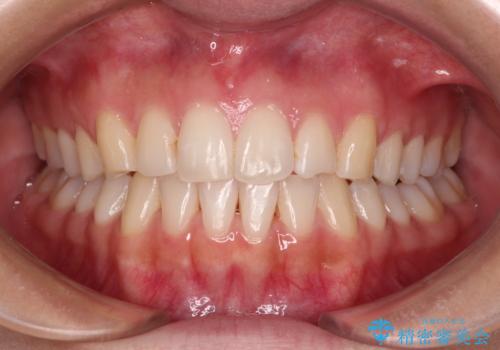

前歯の重なりをインビザライン・モデレートで矯正治療

- 上下前歯の重なりを気にして来院された患者様です。

安価なインビザラインパッケージを用いての治療を希望されており、デコボコの程度が中等度であったため、インビザライン・モデレートを用いて矯正治療を行うこととしました。